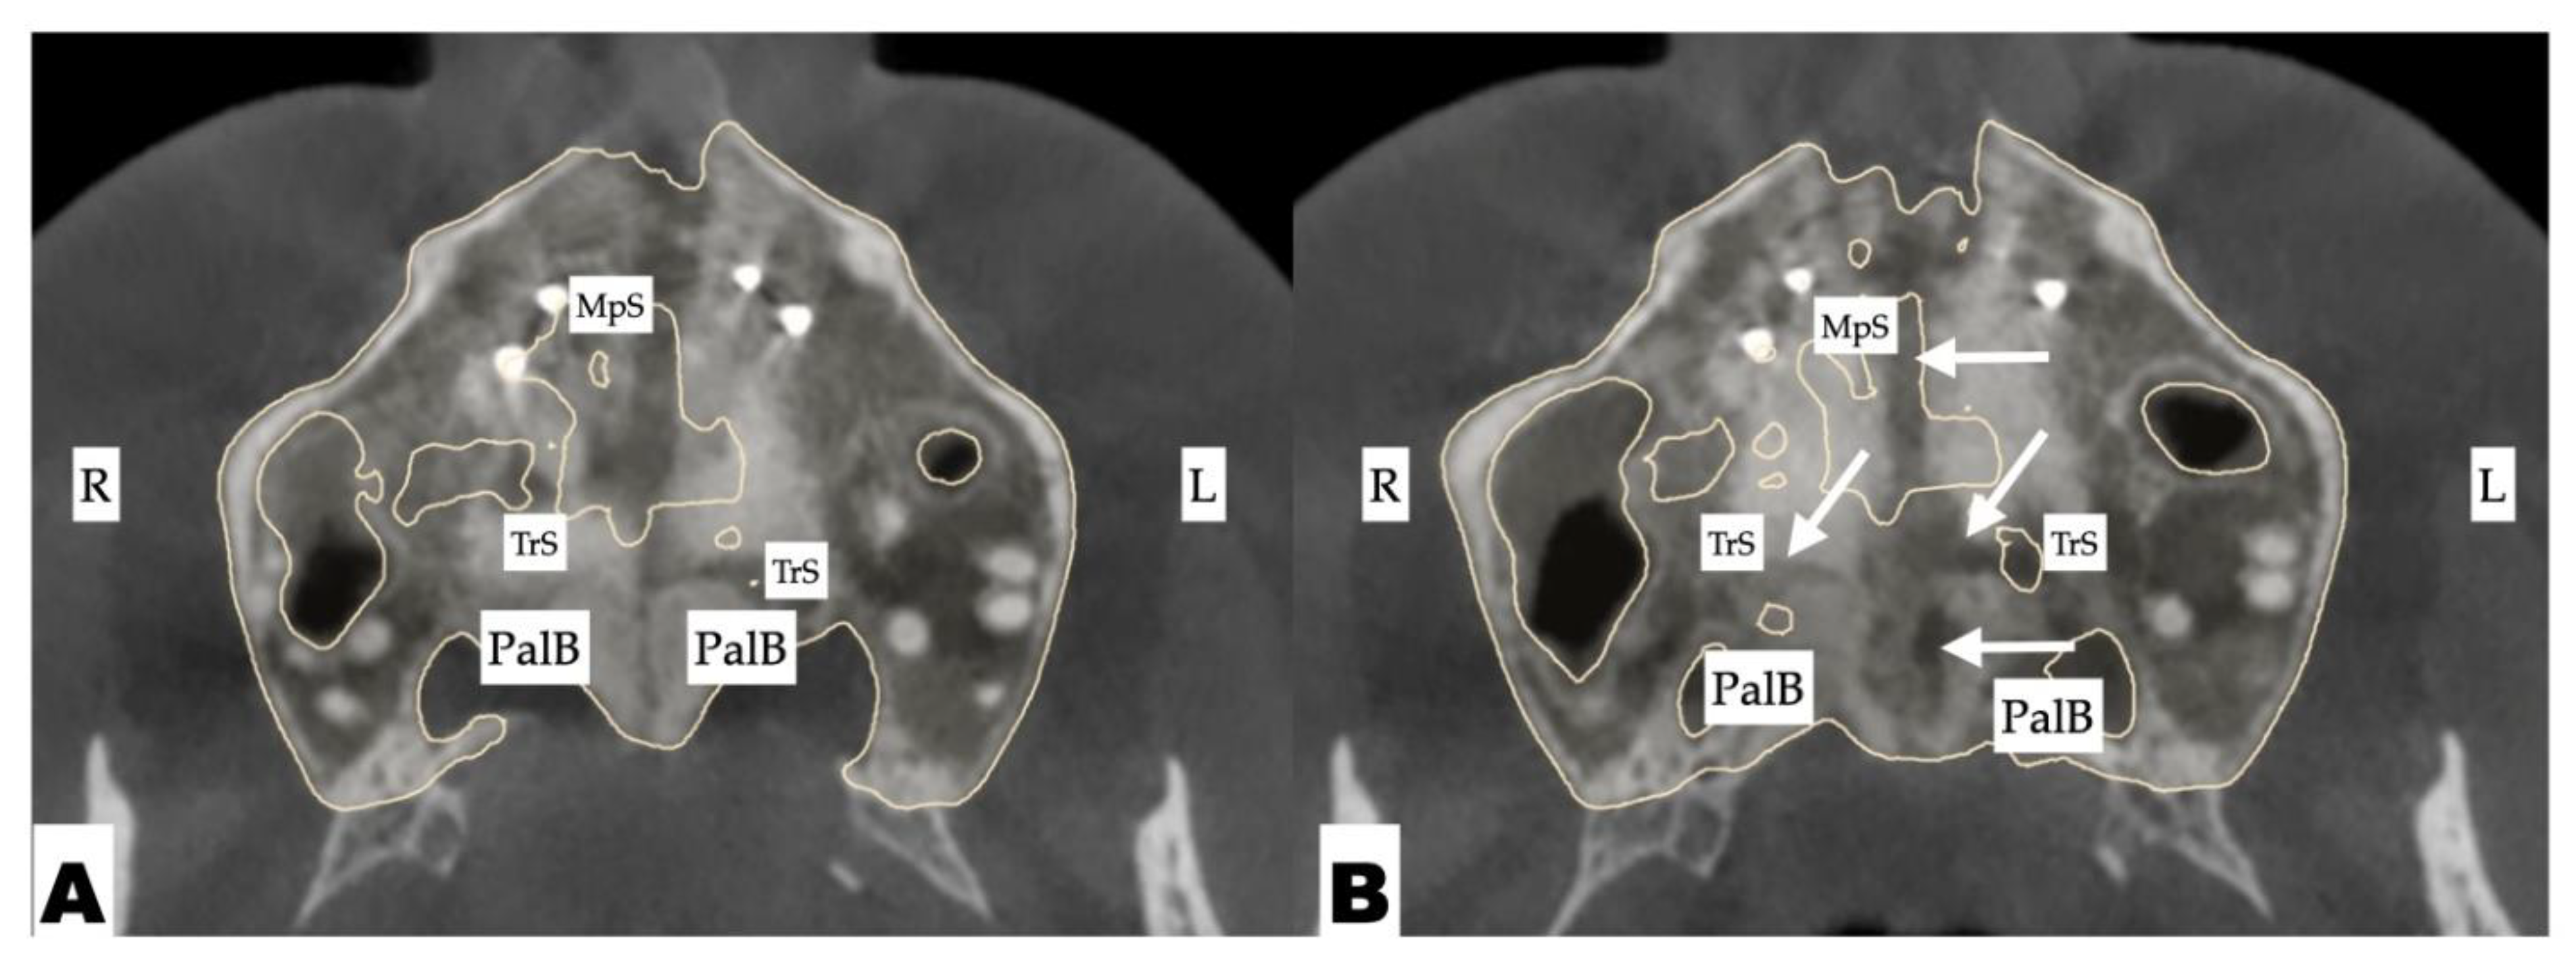

The expansion process lasted for 8 weeks with 1 turn/day, which translates to activation of approximately 0.11 mm/turn. The pattern of midpalatal suture separation was evaluated after the completion of expansion and is shown in Figure 12. The midpalatal suture was completely disarticulated, involving both the ANS and PNS areas. The transverse palatal suture showed signs of disarticulation as well, with the left side having a larger amount of separation.

Figure 12. Disarticulation of the midpalatal and transverse sutures with 3D-guided midpalatal piezocorticotomy-assisted MARPE expansion. Both axial slices show the disarticulation of the transverse suture with a greater degree of separation on the left side. Arrows point to areas of disarticulation. R—Right side; L—left side; MpS—midpalatal suture; TrS—transverse suture; PalB—palatine bone.

Expansion outcome of the current case shows asymmetry in transverse suture separation that was related to the orientation of the screw relative to the course of the transverse suture and midpalatal suture. Further attachment of the jackscrew on the left side has caused greater lever arm for the rotation of the palatal process of the left maxillary bone with its partial forward displacement. This was further accompanied by the proximity of the incisor roots of the left maxillary anterior alveolar process and resulted in perceived antero-posterior discrepancy between the maxillary alveolar process on both sides of the disarticulated midpalatal suture.